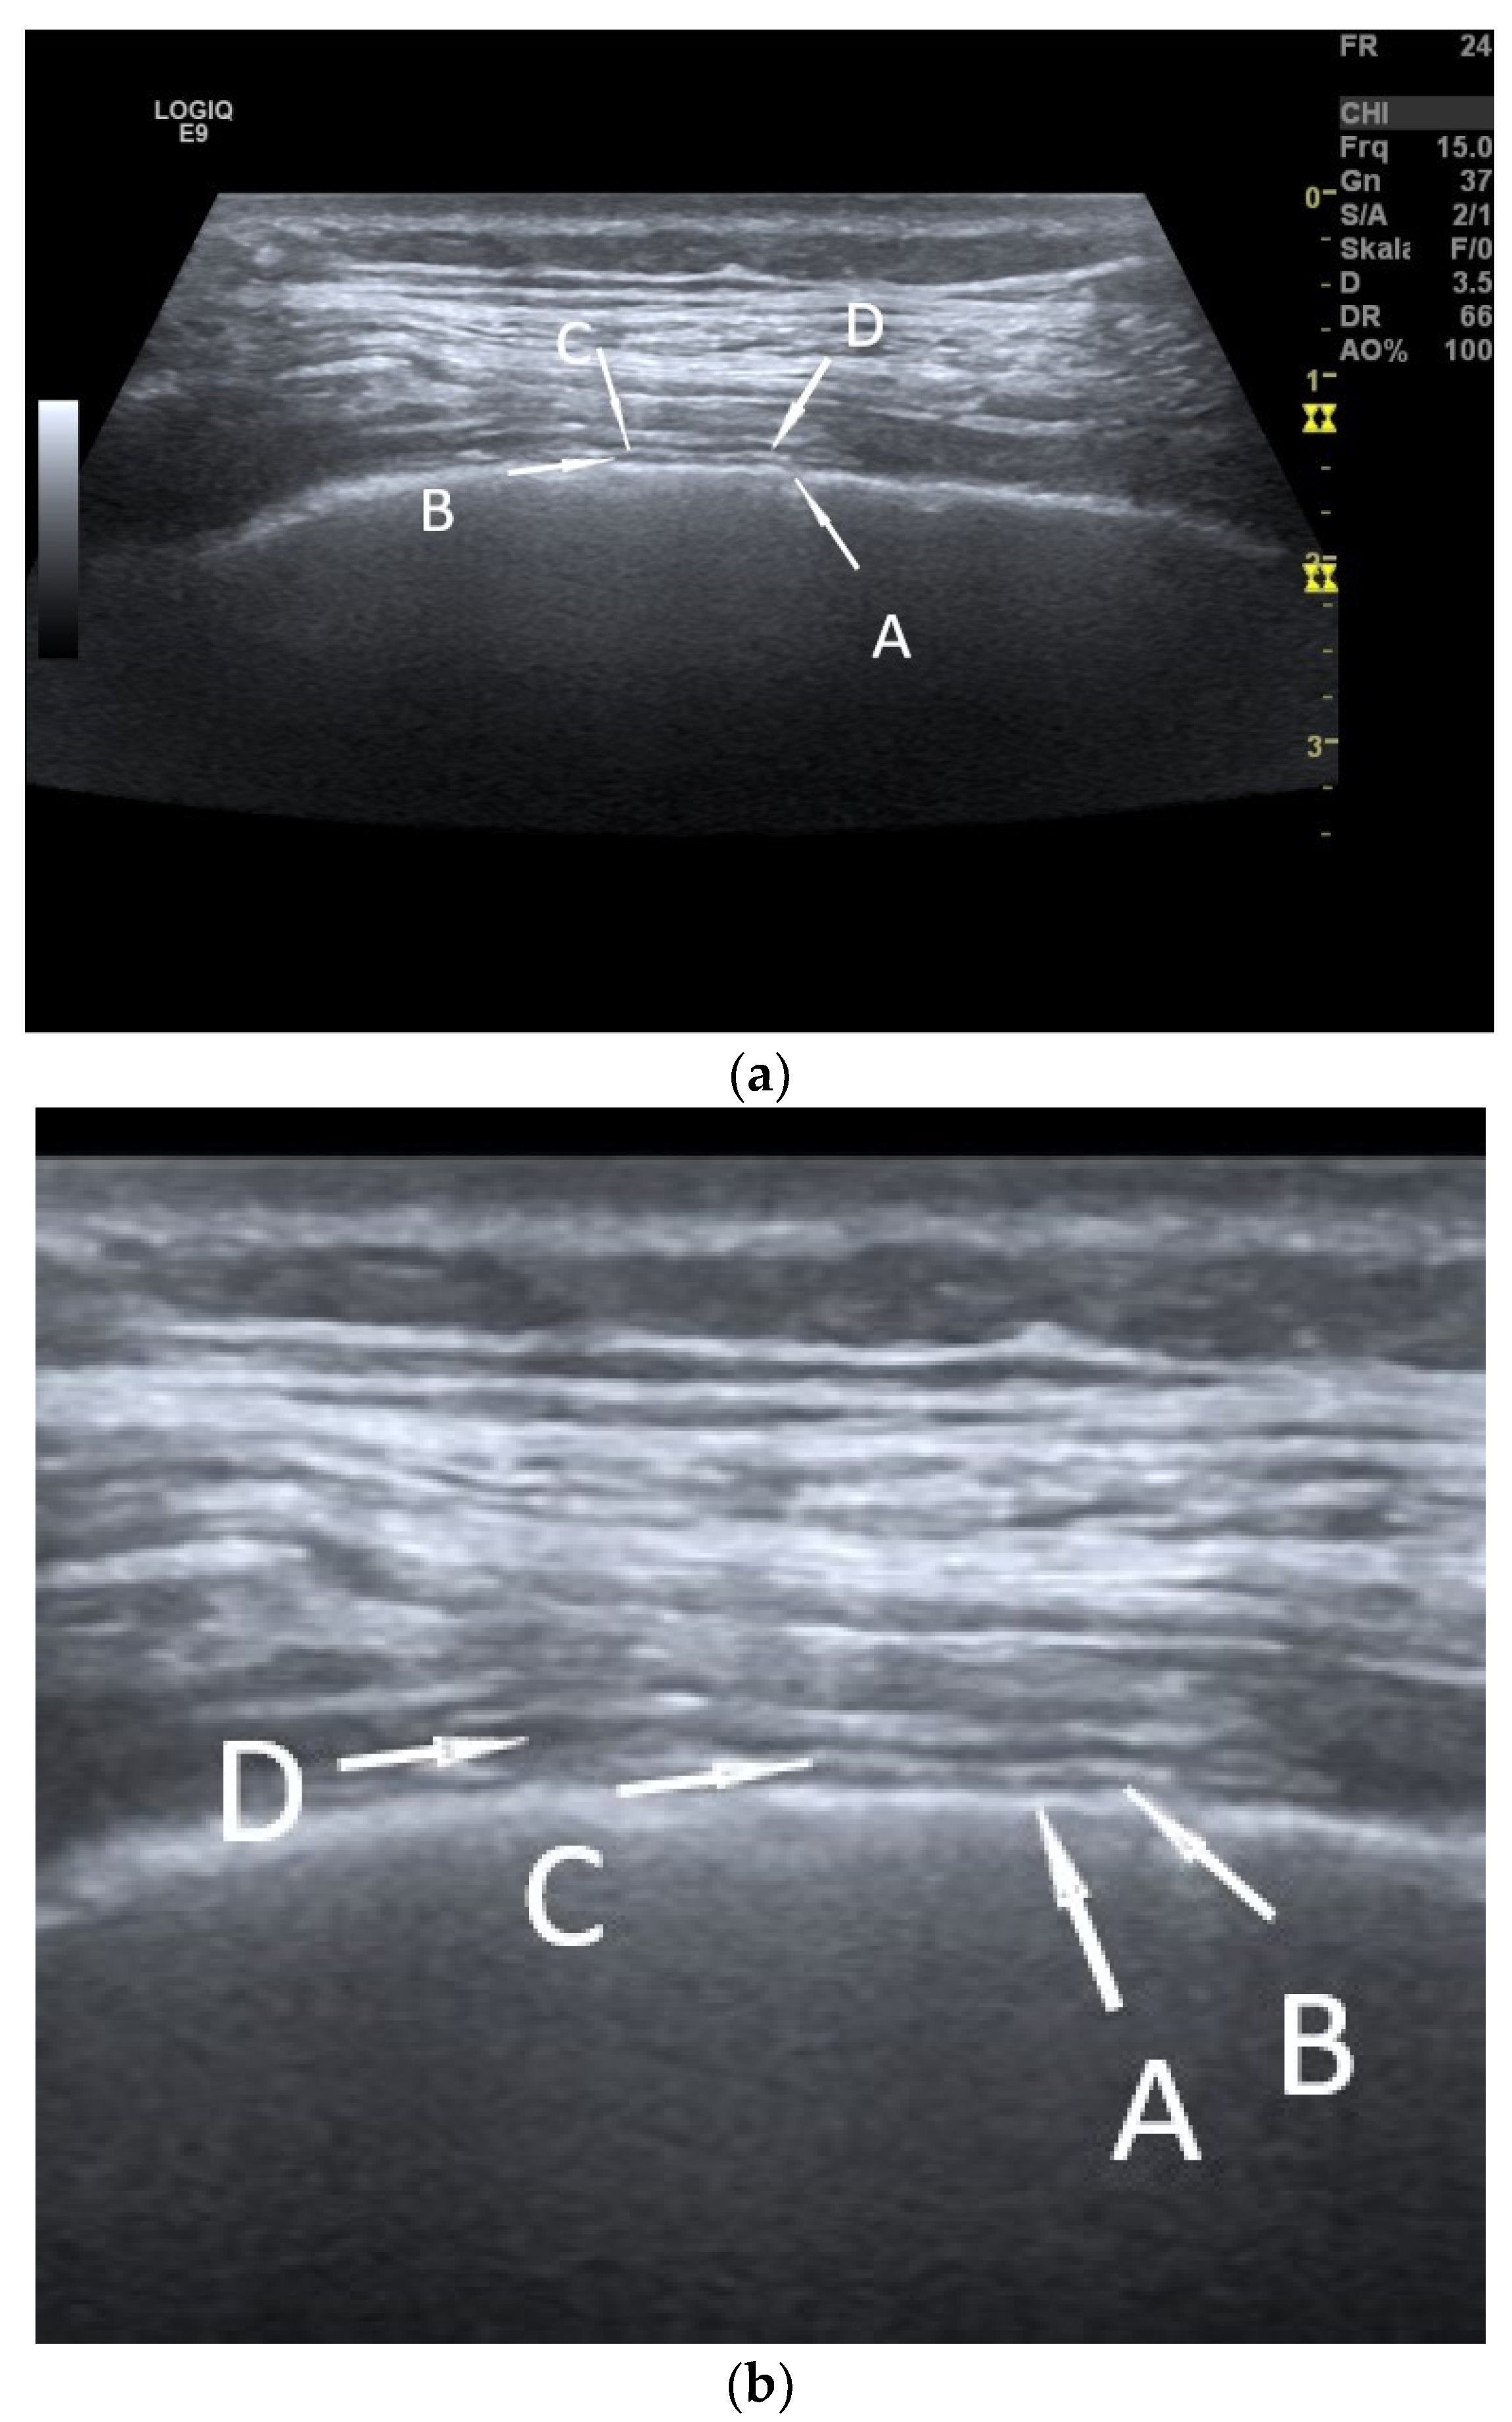

| Fibrothorax | Extensive and dense fibrosis of the visceral pleura, with fusion of the visceral and parietal pleural layers, no lung sliding. |